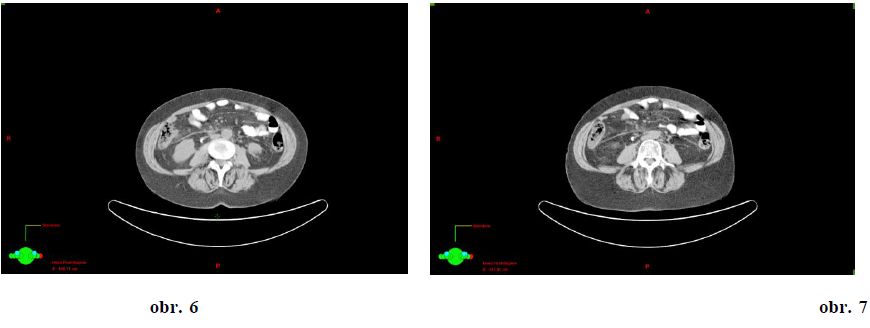

JH r. 1972, dg. 2010 ca mammae l.dx T2 N0 M0, pT2 pN0 pM0, histol.: invazivní duktální karcinom M8500/32, ER 60%, PR70%, Ki67 5%, HER2neu 1+, FISH nebyla nalezena amplifikace, prokázaná mutace BRCA2. Adjuvantní léčba byla ukončena 5/2011. 1. generalizace dle CT 21. 9. 2012 – mnohočetná meta ložiska do obou plicních křídel, největší do 22mm, (Obr. 3)

23. 10. 2012 – zahájena léčba weekly paklitaxel 80mg/m2 + Avastin 10mg/kg á 14 dní CT

(3. 5. 2013) - ložiska svědčící pro neoplazii nenacházíme – CR (obr. 4)

Závěr 1

Pacientka je v kompletní remisi. Léčba Paklitaxelem byla ukončena 3. 5. 2013. Od 4. 6. 2013 pokračuje léčba monoterapií Avastinem 10 mg/kg á 14 dní. Kontrolní vyšetření CT bylo provedeno 12. 7. 2013 – nadále kompletní remise. Další kontrolní vyšetření CT bude provedeno v listopadu 2013.